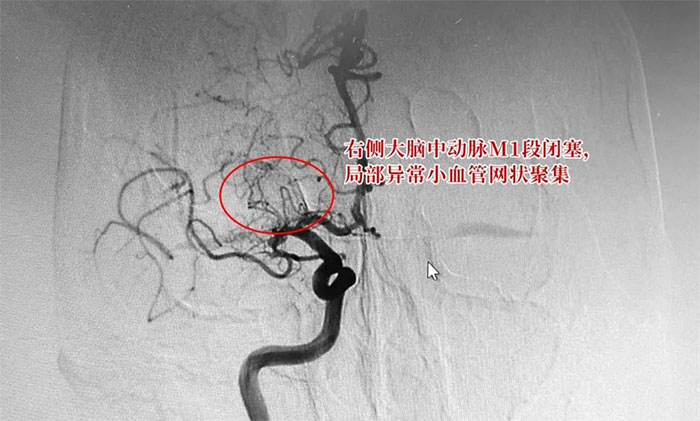

于耀宇主任為患者完善相關(guān)檢查,通過DSA數(shù)字減影血管造影,患者雙側(cè)大腦中動脈部分區(qū)段存在不同程度狹窄,尤其是右側(cè)大腦中動脈M1段閉塞,局部異常小血管網(wǎng)狀聚集。

▲ DSA檢查示:右側(cè)大腦中動脈M1段閉塞,局部異常小血管網(wǎng)狀聚集